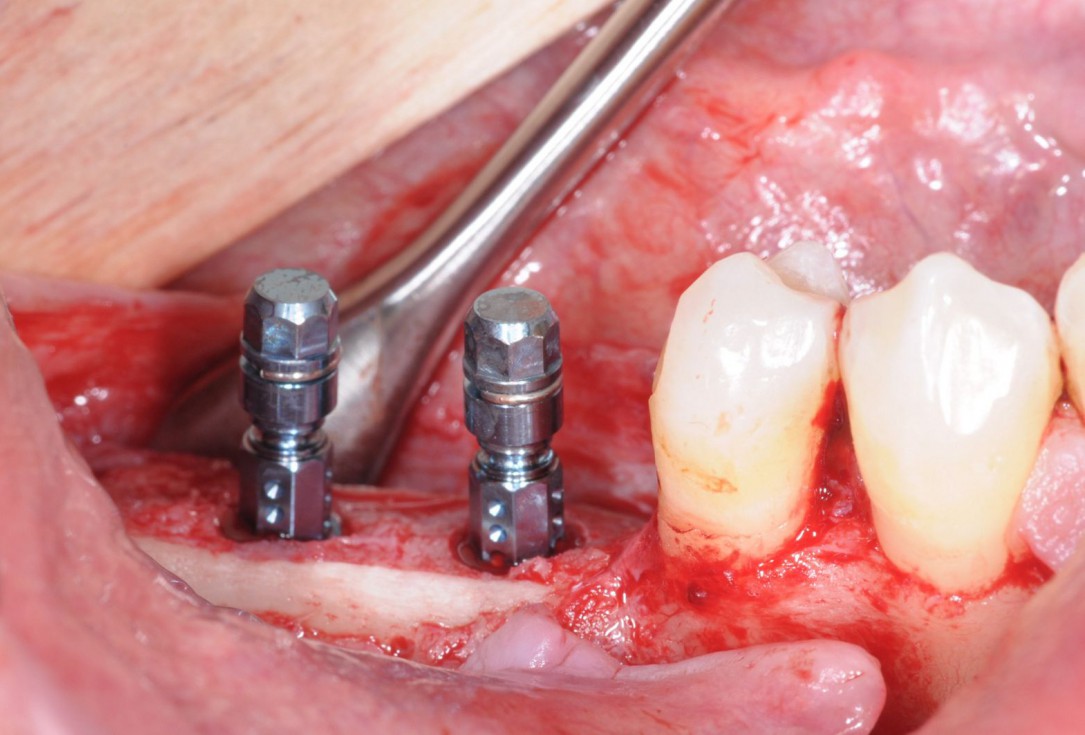

18/28 - Implantation of two Straumann BLT implants into the augmented boneThree-dimensional augmentation with maxgraft® cortico - Dr. R. Würdinger

19/28 - Placement of implant cover screws in the fully submerged dental implantsThree-dimensional augmentation with maxgraft® cortico - Dr. R. Würdinger